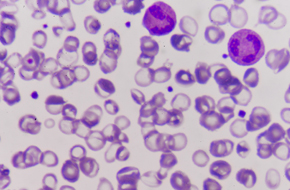

Whatever your project needs, we have the in vitro biology platform to support faster, better decision-making for your oncology drug discovery program.

Our expert team have extensive experience of working with companies to support the in vitro pharmacology characterization of lead compounds and are committed to saving you precious time and resources by providing efficient screening platforms and validated 2D and 3D models, giving you confidence in your data.

Utilize the XenoBase®, the world’s largest commercial database of well-characterized cell lines to choose the correct cell lines for in vitro evaluation of your novel molecules.

Use cost-effective, rapid, and large-scale cancer cell line screening to advance your lead compound to validated candidate